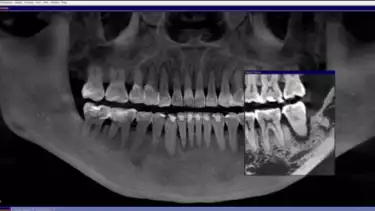

Sebaliknya, hasil rontgen pada gigi kiri menunjukkan kerusakan yang lebih signifikan. Tulang hampir tidak lagi melekat pada gigi, menyebabkan giginya lebih goyang dan sulit dipertahankan. “Potensi pemulihan gigi sebelah kiri jauh lebih rendah, dan kemungkinan keberhasilannya lebih kecil. Namun, kami tetap berupaya mempertahankan gigi semampu mungkin,” tambah drg. Devya.